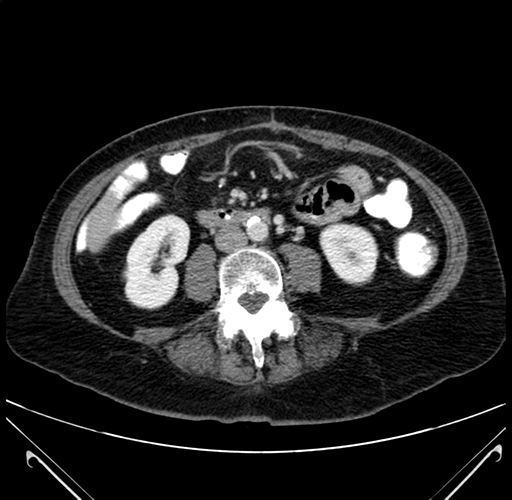

Axial Venous

Coronal Venous